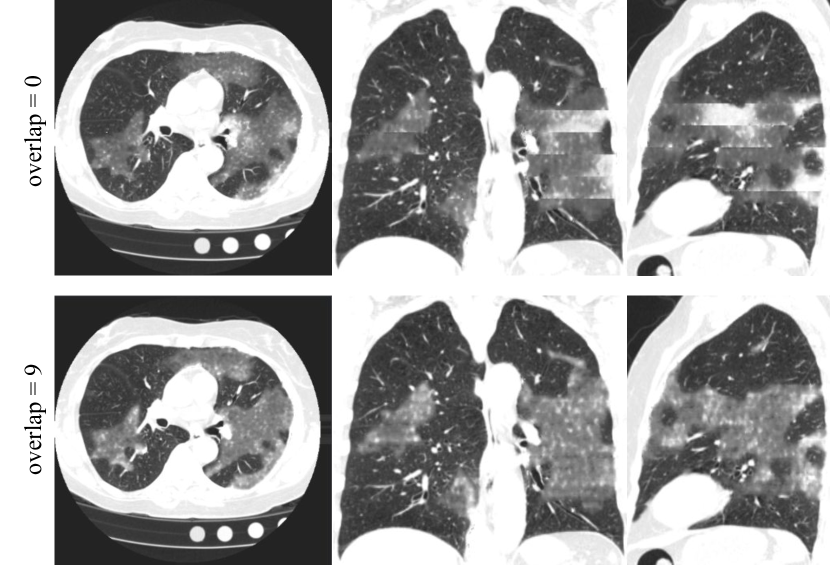

Refer to caption

Figure 2: The example slices of the model output with input overlap = 0 and overlap = 9. From left to right are the example slices of axial, coronal and sagittal views. The 3D volume predicted with overlap = 9 shows better consistency along the z dimension.